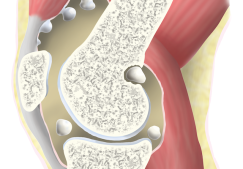

Эндопротезирование голеностопного сустава – перспективное, но мало изученное направление. Реконструкция этой части опорно-двигательного аппарата, как бы хорошо она ни была проведена, все равно потенцирует возникновение вторичного деформирующего артроза. Риск осложнения – результат следующих факторов:

- дополнительного повреждения во время хирургического вмешательства;

- нагрузки на околосуставные ткани и их травмирование;

- ухудшение суставной трофики в период послеоперационного восстановления.

Клиническое наблюдение в больницах Европы позволило сделать вывод, что на протяжении длительного времени использования хорошо зарекомендовали себя эндопротезы марки S.T.A.R. производства фирмы WALDEMAR LINK GmbH & Co. KG (Германия), Mobility™ (DePuy, Англия), марки HINTEGRA (New Deal SA, Франция).

У 15 пациентов со сроком наблюдения 6,2 года удалось установить признаки нестабильности и преждевременного износа компонентов протеза. Выполненное исследование показало: наибольшая выживаемость эндопротеза – у пациентов с ревматоидным артритом и у лиц со сниженной двигательной активностью.

Преимущества современных эндопротезов:

- Костный цемент, применяемый в процессе фиксации, не выдавливается за пределы эндопротеза при его установке.

- Усовершенствованные модели имплантов исключают необходимость проведения резекции значительной площади суставных поверхностей. Учитывая этот фактор, губчатая кость представляет собой достаточно надежную опору для закрепления костного цементного материала.

- Не происходит перемещения имплантатов. Протез не мигрирует в дистальный метаэпифиз большеберцовой кости или тело таранной кости.

- Хирургическая травма не провоцирует слабое заживление послеоперационной раны.

- Минимальное число неблагоприятных исходов.

Интерес к эндопротезированию голеностопного сустава вернулся сразу после внедрения бесцементных имплантатов, совершенствования дизайна (стали практиковать имплантацию трехкомпонентных моделей), нормализации качества операционного инструментария.